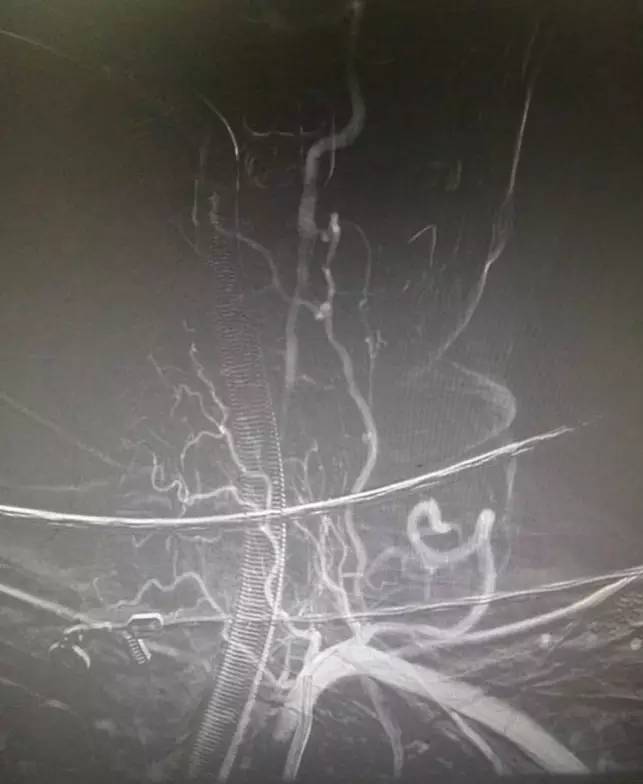

▼右椎动脉造影见基底动脉末端闭塞。双侧颈内动脉造影无殊,双侧后交通未见显影。

▼支架释放后,右大脑后及小脑上显影同时看到基底动脉的血栓,拉栓一次就再通。